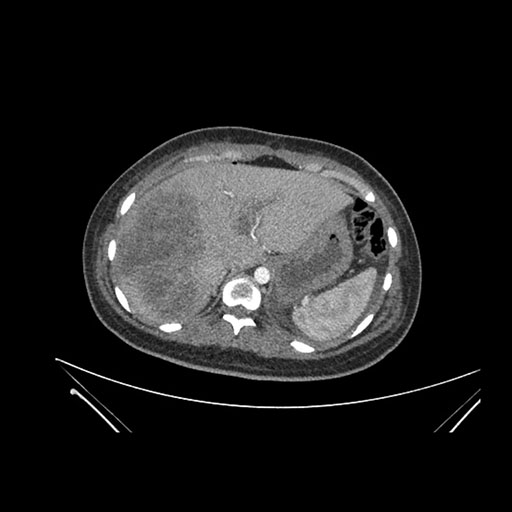

Vasculobiliary injury [M28]

Imaging Analysis

Look through the patient's CT scan to identify any areas of concern for the necessary procedure.

Axial Arterial

Axial Venous